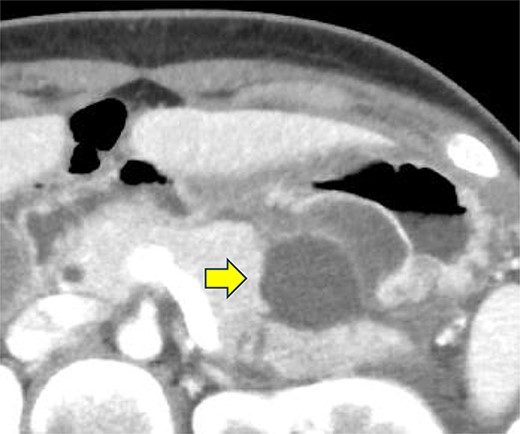

A 19-year-old woman who had fallen from a bicycle and bruised her upper left abdomen with handlebars presented to our emergency department 18 h after the injury with persistent abdominal pain. She was admitted with a diagnosis of pancreatic injury, as evidenced by elevated pancreatic amylase (P-Amy) levels (779 IU/L) and contrast-enhanced computed tomography (CT) showing a linear area with poor contrast in the pancreatic body (Fig. 1). Physical examination revealed a flat abdomen with mild tenderness in the upper left quadrant. Biochemical blood tests revealed elevated inflammatory markers; white blood cell count 10 950/μl, and C-reactive protein 0.58 mg/dl. On the fourth day, white blood cell count elevated to 21 940/μl and C-reactive protein elevated to 32.7 mg/dl. Contrast-enhanced CT revealed fluid accumulation, indicating pancreatic pseudocyst, primarily in the ventral pancreatic body and extending toward the spleen, along with edematous thickening of the adjacent stomach wall (Fig. 2).

Contrast-enhanced CT of the abdomen on the fourth day. Fluid accumulation (pancreatic pseudocyst) was observed, primarily located on the ventral pancreatic body and extending toward the vicinity of the spleen, along with edematous thickening of the adjacent gastric posterior wall.